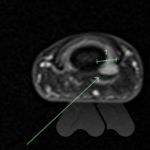

Carpal tunnel syndrome affects the median nerve that travels through a space that connects the forearm and hand at the front of the wrist. Pressure on the nerve, from many possible causes, can lead to a slowing of the electrical signals that supply sensation to the thumb, index and middle finger. It can lead to tingling and numbness in these fingers or the whole hand and can often be worse at night time.